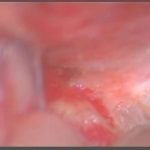

手術前1

手術前2